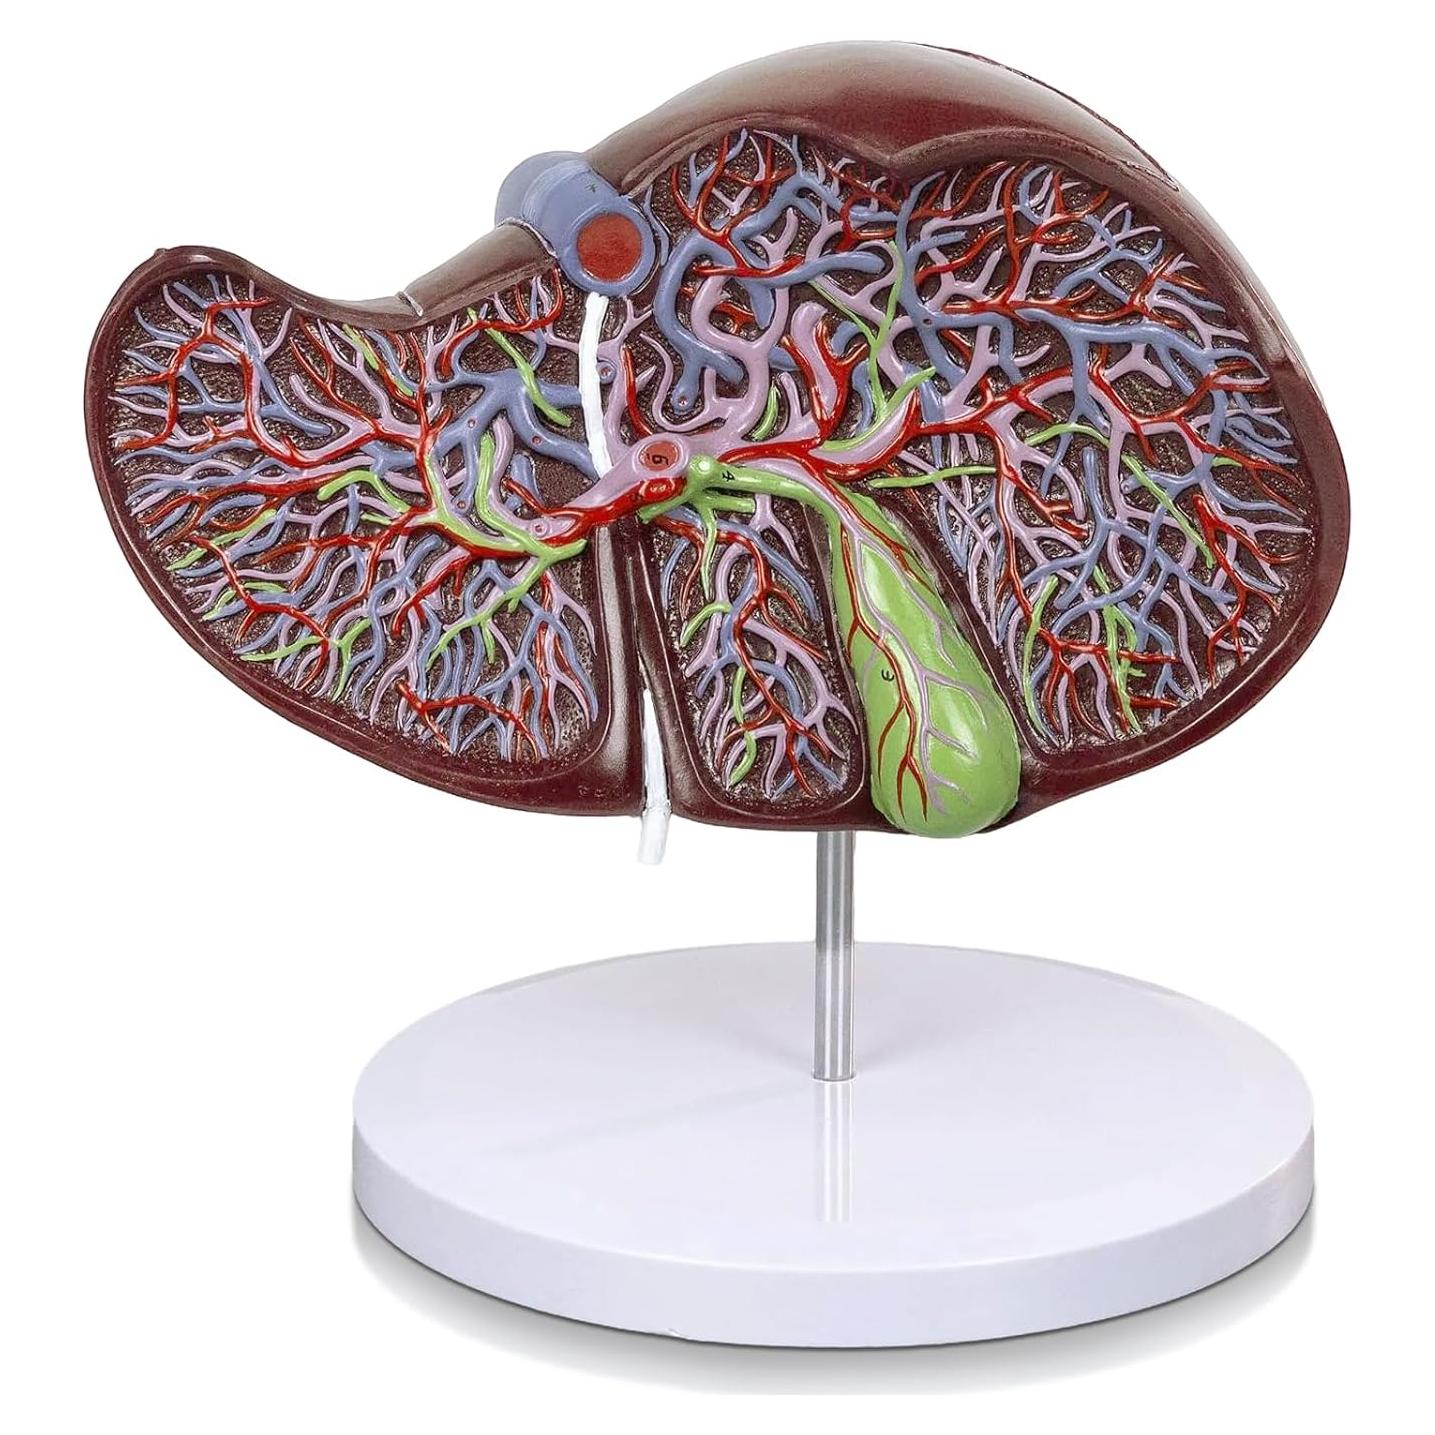

Modelos Anatómicos de Órganos marca Evotech (20 productos)

Modelos Anatómicos 3D EVOTECH SCIENTIFIC - Cuerpo, Corazón y Esqueleto